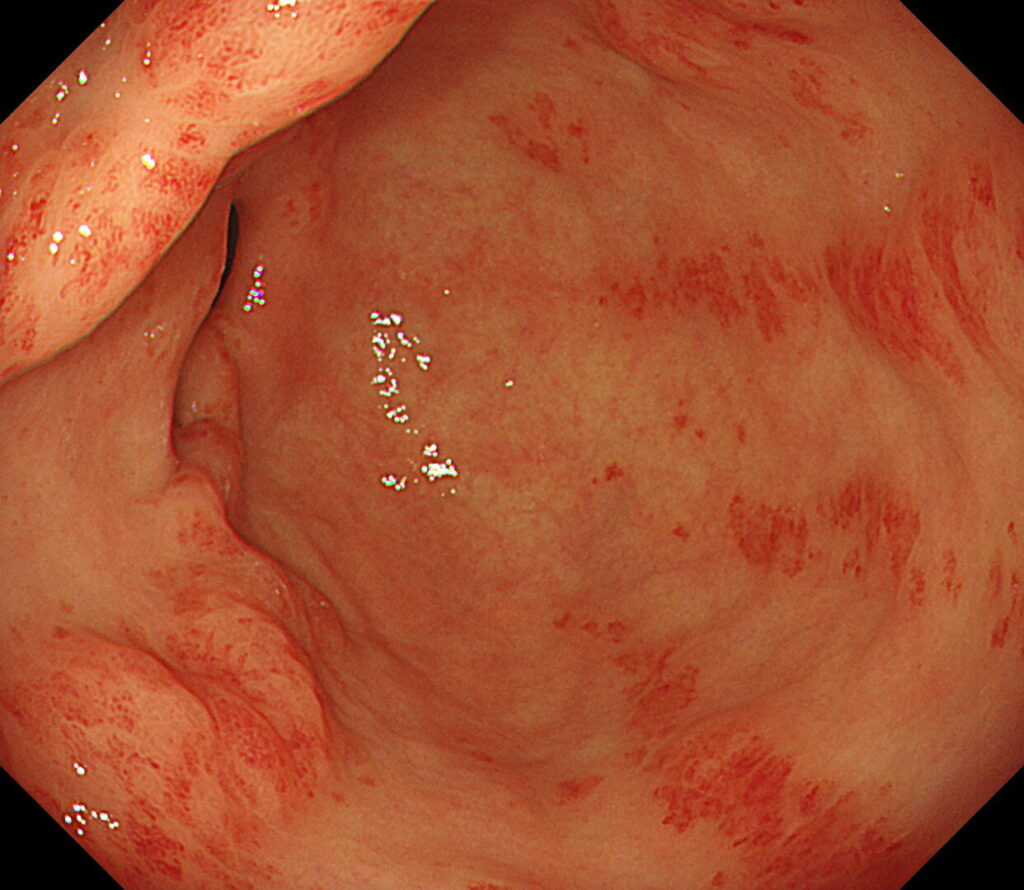

- 점막이 붉거나 부종이 심한 경우

- 표면이 거칠거나 미세한 융기, 함몰이 발견되는 경우

- 미란, 궤양, 백태성 변화 등이 관찰되는 경우

- 장상피화생이 의심되는 구조 변화가 있는 경우

위내시경에서 보이는 병변은 일반적으로 ‘정상’, ‘염증’, ‘선종’, ‘암’으로 구분되지만, 실제 점막 내부의 세포 변화는 훨씬 다양하고 복잡합니다. 육안 관찰만으로 선종인지 단순 염증인지, 조기 위암인지 구분이 어려운 경우가 많기 때문에 조직검사가 정확한 확진을 내리게 됩니다.

내시경에서 ‘위염’으로 보이는 대부분의 병변은 조직검사를 통해 형태학적 분류가 가능해지고, 위축 정도와 화생 여부에 따라 위암 발생 위험도를 평가할 수 있습니다.

위축성 위염 및 장상피화생 평가

- 위점막의 얇아짐, 창백함

- 위산 분비 감소

- 장점막 형태가 나타나는 변화

이 두 가지 변화는 위암의 전구 병변으로 간주되기 때문에 정기적인 조직검사 추적이 중요합니다.